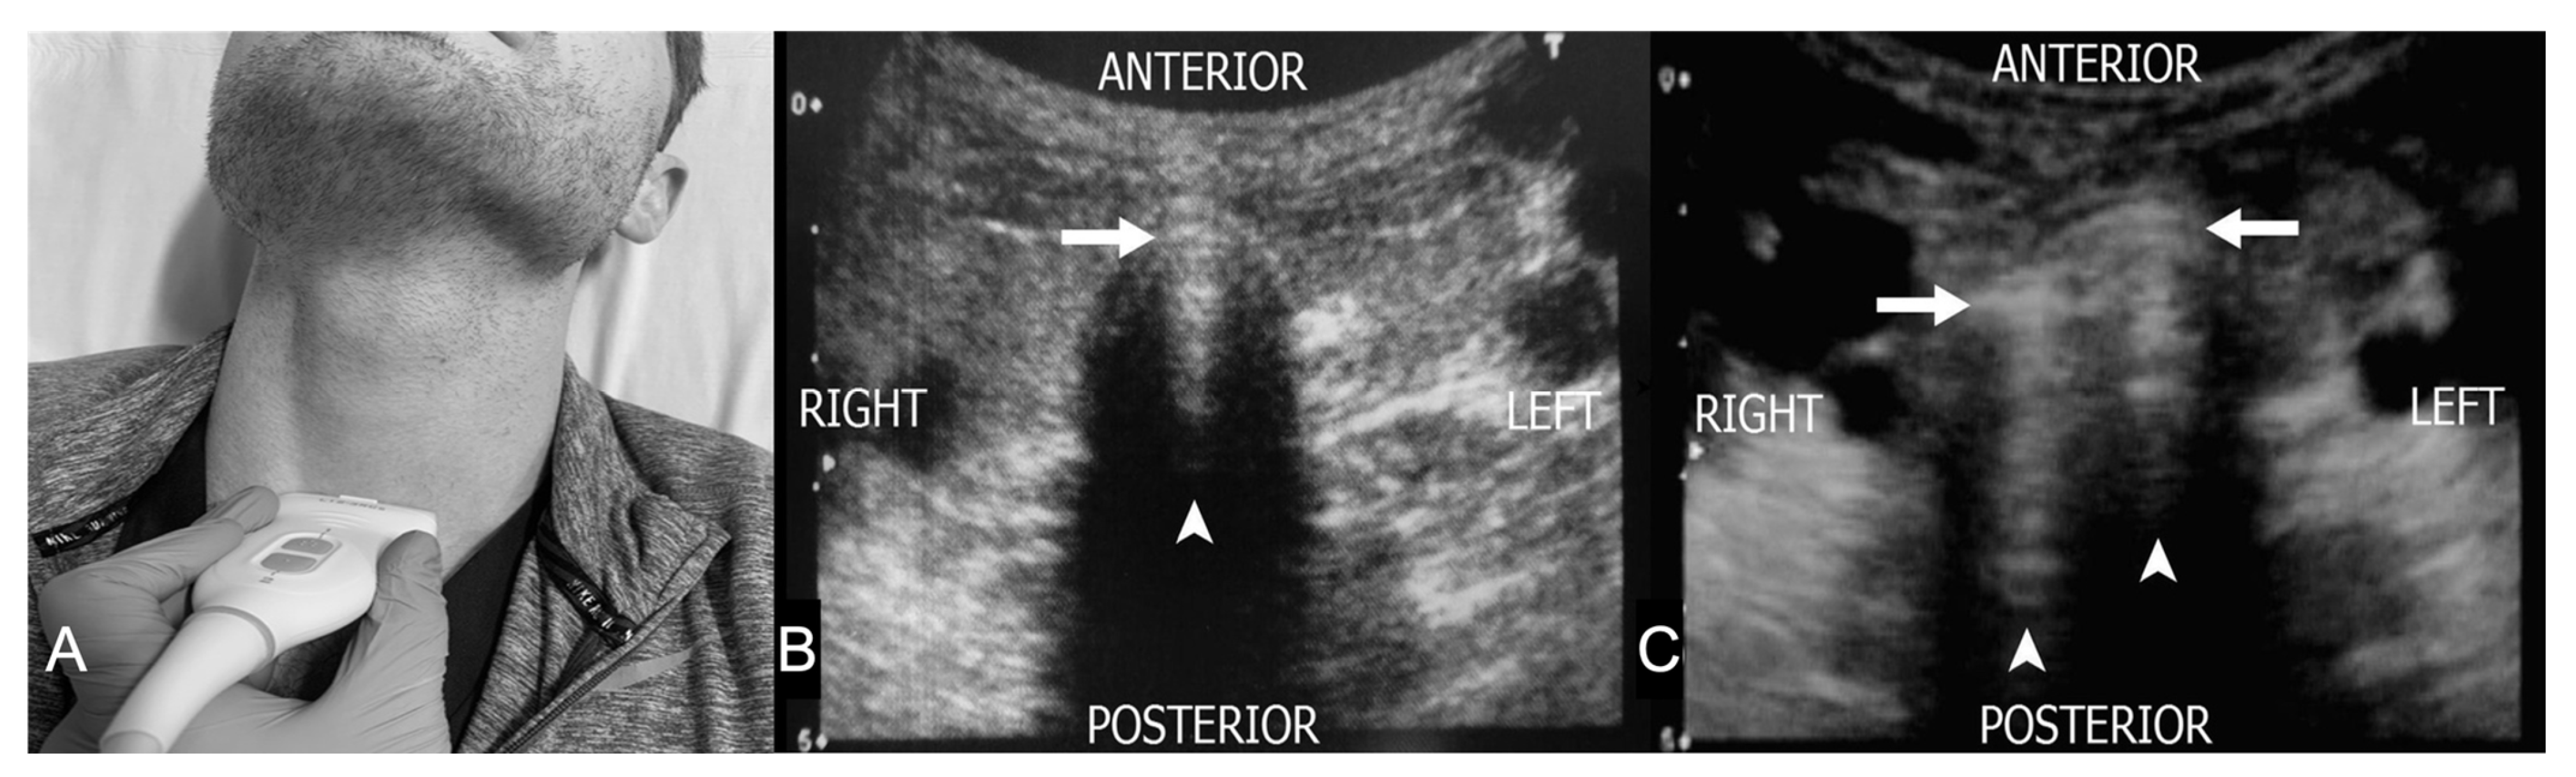

6. Confirmation of Endotracheal Intubation

7. Assessment of Laryngeal Edema